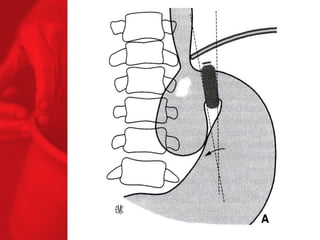

LA DIVERSION BILIO-PANCREATIQUE(DBP) Procédure de malabsorption Poche de l'estomac plus grande Plus grande perte de poids Plus grande malabsorption des nutriments Perte de surcharge pondérale de 74% la première année, 78% la deuxième année, 81% la troisième année, 84% la quatrième année et 91% la cinquième année*. diminue le diabète de type 2 chez près de 77% des patients** *Duodenal Switch: An Effective Therapy for Morbid Obesity – Intermediate Results” Baltasar A, Bou R. Obesity Surgery 2001 Feb; 11(1): 54-8. ** Buchwald H, Avidor Y, Braunwald E, et al. Bariatric Surgery—A Systematic Review of the Literature and Meta-analysis. Journal of the American Medical Association 2004 Oct 13;292(14).

COMMENT FONCTIONNE LADBP ? Facteurs chirurgicaux Restriction du volume des repas Malabsorption élevée Facteurs pour les patients Apport en calories Dépense en calories BILAN ENERGETIQUE = apport alimentaire dépense en énergie